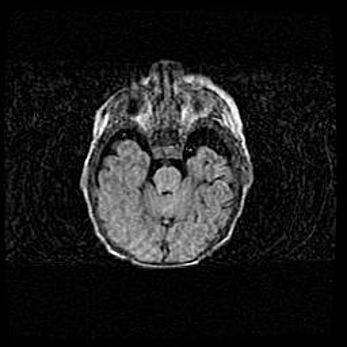

Церебральная ишемия II.

Возраст: 5 дней

Вес: 3400 г

Пол: женский

Окружность головы: 35 см

Срок гестации: 39 недель

Церебральная ишемия – это заболевание, характеризующееся недостаточностью (гипоксией) либо полным прекращением (аноксией) снабжения мозга кислородом по причине закупорки одного или нескольких сосудов. Это приводит к  что метаболическим расстройствам различной степени тяжести в тканях головного мозга, развитию коагуляционных некрозов и гибели нейронов.